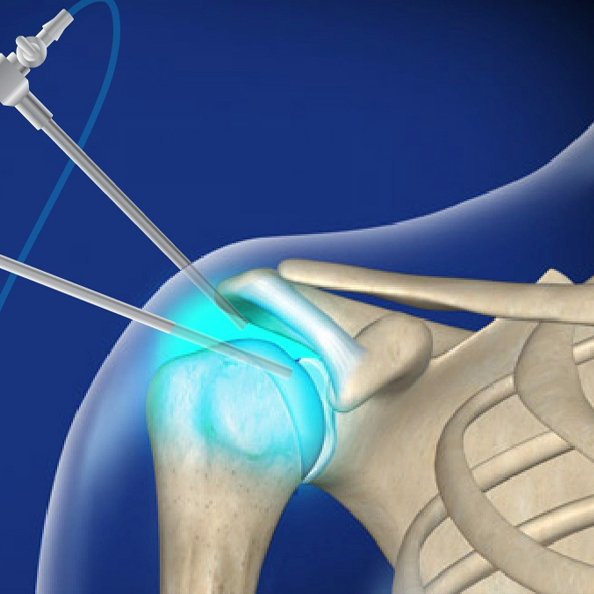

Shoulder Arthroscopy Surgery

Advanced shoulder arthroscopy procedures to treat Rotator Cuff Tears, Bankart Injury, Hill Sachs Lesion, with Repair, Remplissage & Biceps Tenodesis or Tenotomy, restoring mobility with quicker, less invasive recovery options.